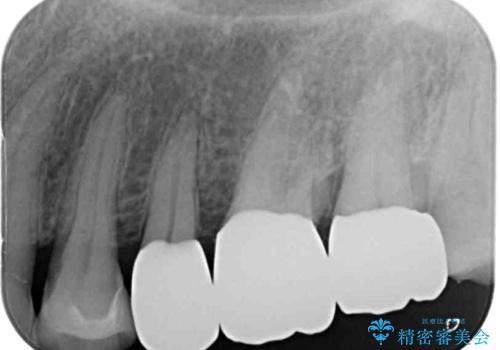

知覚過敏の症状が強い歯と、銀歯の範囲や銀歯の下のむし歯が大きい歯は、インレー修復では対応が難しいためオールセラミッククラウンで、インレー修復で対応が可能な歯ではセラミックインレーにて修復することとしました。

知覚過敏の症状はなくなり、希望通りの白い歯になったと、患者様は大変満足されました。